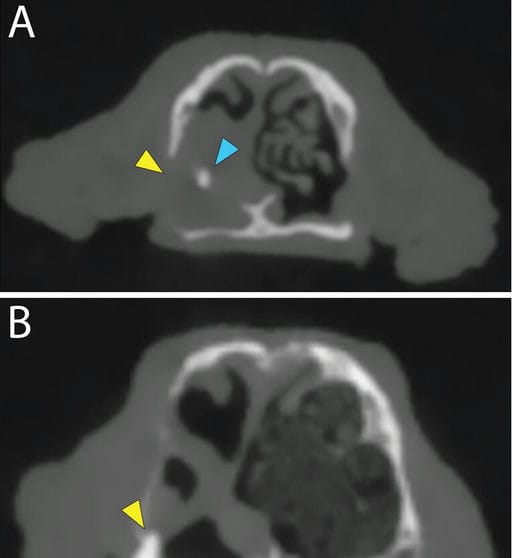

Cone-beam CT axial view (A) of a canine skull in a middle-aged spayed female Yorkshire Terrier mix presenting for persistent ONC after a failed surgical attempt of closure at the level of the left maxillary canine tooth. Note the ONC at the level of the absent left maxillary canine tooth (A; yellow arrowhead) and the hyperattenuating foreign body within the left nasal cavity (A; light blue arrowhead). Also note the ONC at the level of the left maxillary second premolar (B; yellow arrowhead) and the associated turbinates’ destruction and nasal mucosa thickening, consistent with rhinitis. Panels are represented in a bone window (window width, 2,500 HU; window level, 1,480 HU) with a 0.5-mm slice thickness.